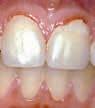

Det er velkendt, at ortodontiske behandlinger øger risikoen for at udvikle caries, især de kosmetisk skæmmende læsioner, der udvikler sig pga. de kunstige plakstagnationsområder omkring brackets (4-6). Disse læsioner kan være svære at maskere efter den ortodontiske behandling (5,6).

Internationale studier samt klinisk erfaring i Danmark viser, at børn og unge under ortodontisk behandling ofte udvikler caries i form af white spot lesions (WSL) omkring det ortodontiske apparatur. Dette RCT-studie demonstrerer tydeligt, at fluoridskylninger 2 x ugentlig med en 0,32 % natriumfluoridopløsning (~ 1.450 ppm fluorid) har en signifikant cariesreducerende effekt på prævalensen af WSL på testgruppens deltagere i forhold til kontrolgruppens (placeboopløsning) deltagere efter 12 måneders observationstid.